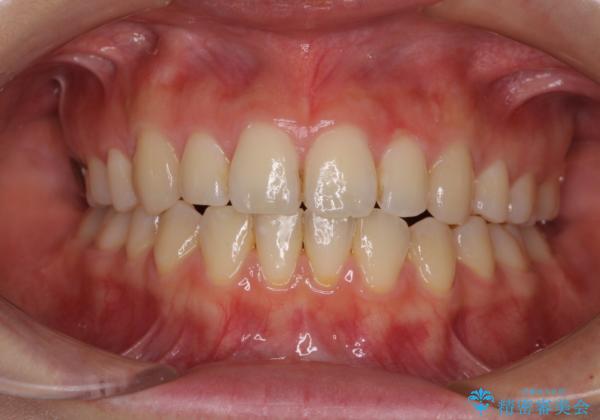

- 前歯のデコボコを気にして来院された患者様です。

本人は気づいていませんでしたが、下顎前歯が2本欠損しており、上下の歯列がアンバランスとなりデコボコになっていました。

上下のバランスを取るため、上顎左右第一小臼歯2本を抜歯し、ワイヤー矯正を行うこととしました。

抜歯矯正を行ったことで、デコボコが改善されただけでなく、口元も下がったことで口が閉じやすくなりました。